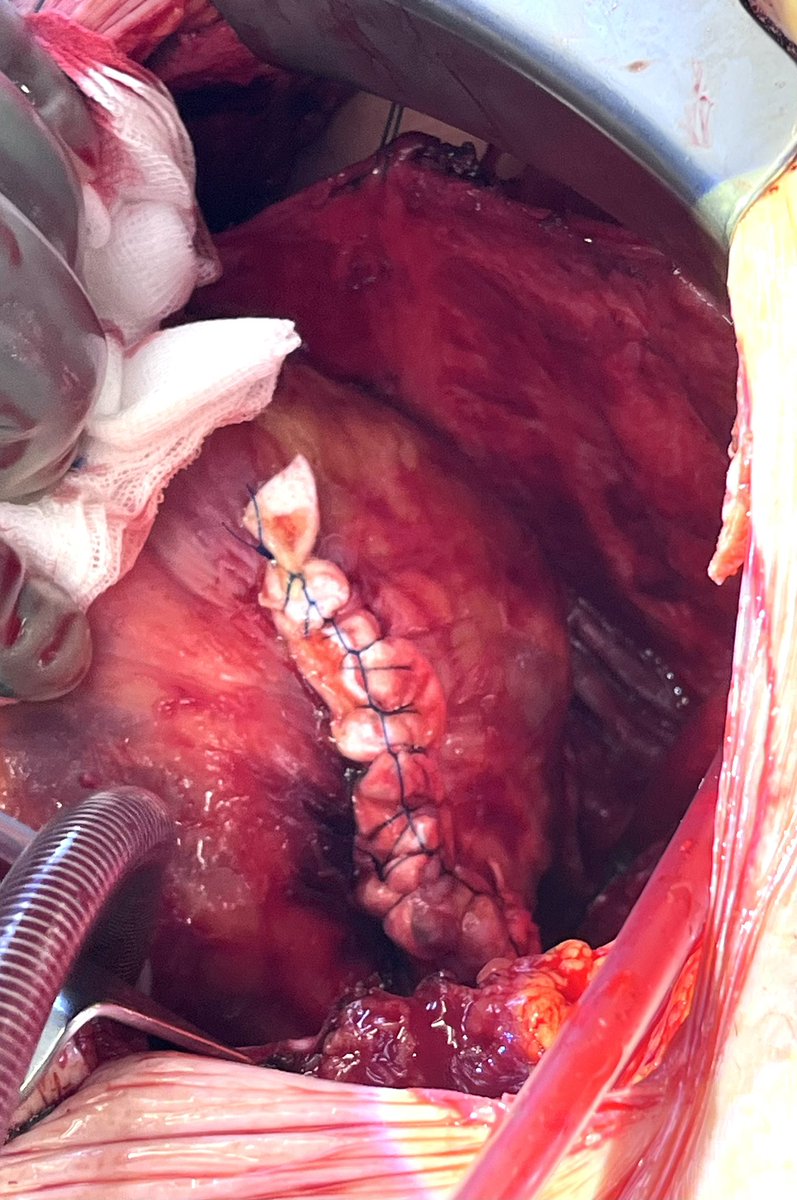

The AMDS-Stent is a very good option in treating acute aortic type A dissection Stretching the felt during performing the anastomosis might be one key of success avoiding aortic stenosis and collapsing . Many thanks to Davide de Manna for sharing the illustrations.

The  AMDS-Stent is a very good option in treating acute aortic type A dissection

Stretching the felt during performing the anastomosis might be one key of success avoiding aortic stenosis and collapsing . Many thanks to Davide de Manna for sharing the illustrations.